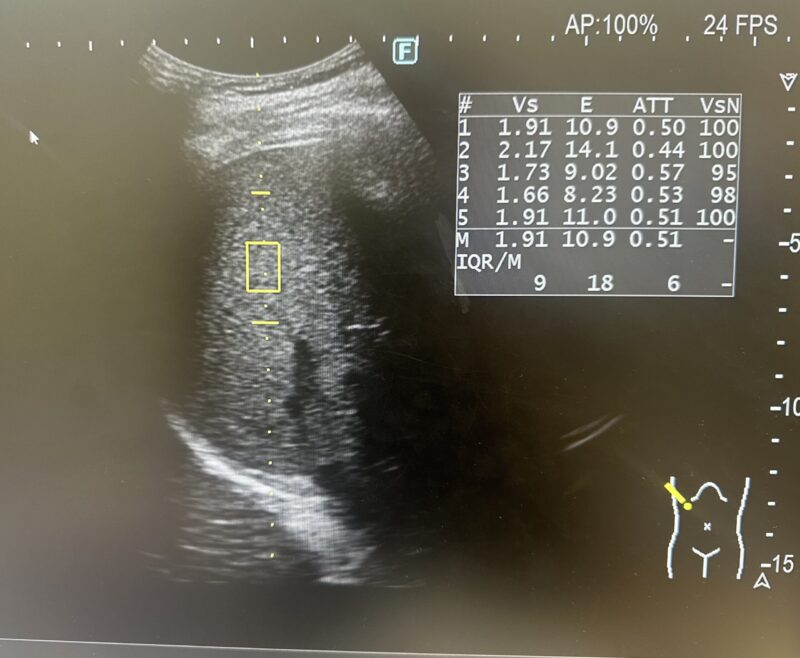

検査お疲れでした。当院で行ったエコー検査の検査項目についてご説明します。 脂肪肝、肝硬度の測定について 肝障害などによりおこなう腹部エコーで、必要に応じて肝硬度と脂肪化を測定します。測定した場合はレポートに下のような画像が添付されています... -